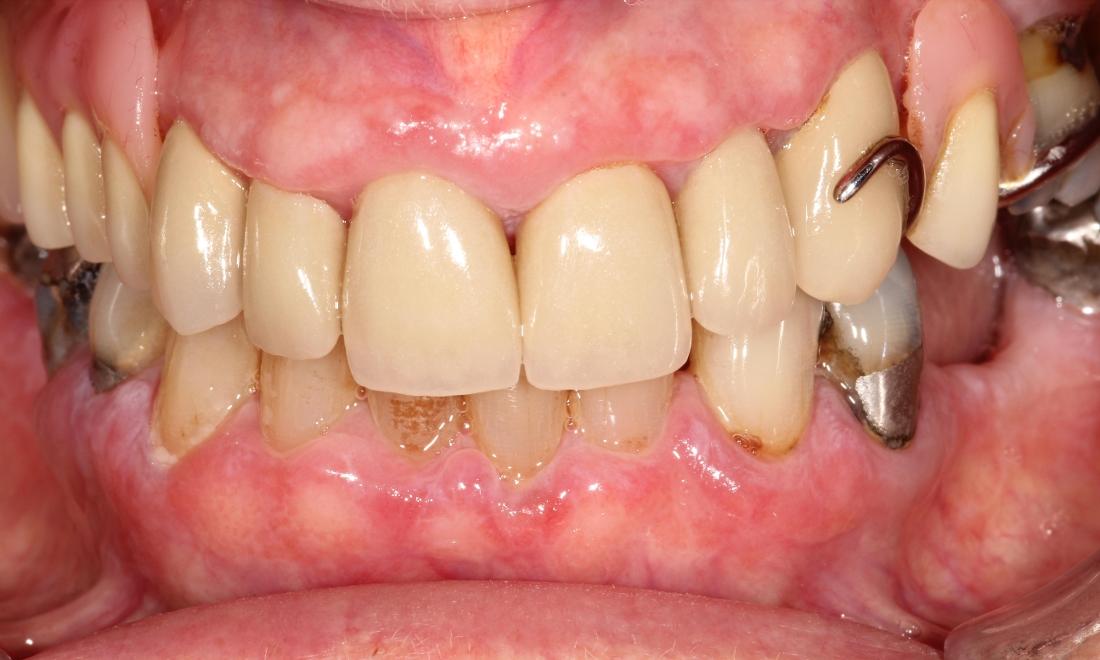

Crown Restorations

Upper (maxillary) crown work completed around upper partial denture. We removed the decay in these teeth, prepped them, and placed six anterior crowns for a beautiful result!